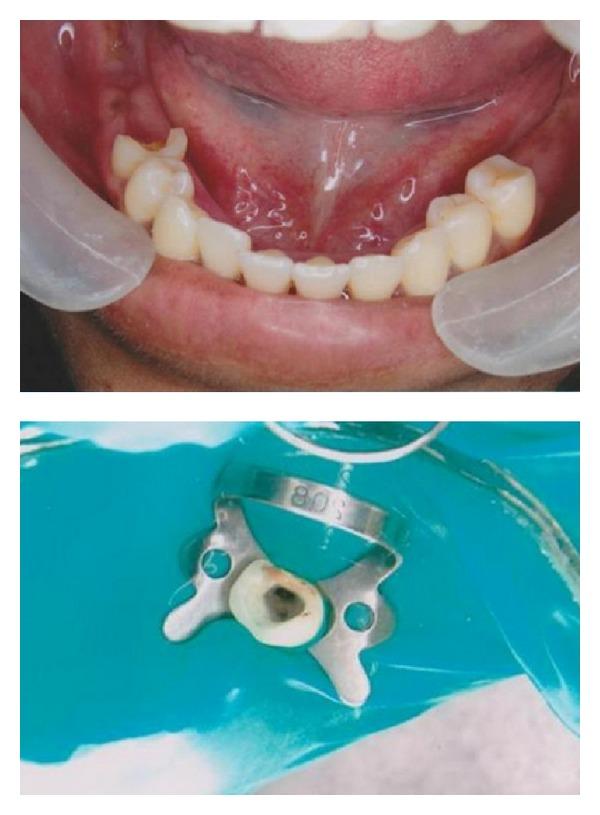

Anatomic and internal morphology of a root canal system is more complex and differs for each individual tooth of which mandibular premolars have earned the reputation for having aberrant anatomy. The occurrence of three canals with three separate foramina in mandibular second premolars is very rare. A wider knowledge on both clinical and radiological anatomy especially spiral computed tomographic is absolutely essential for the success of endodontic treatment. These teeth may require skillful and special root canal special shaping and obturating techniques. This paper reports an unusual case of a mandibular second premolar with atypical canal pattern that was successfully treated endodontically.

根管系统的解剖结构和内部形态更为复杂,每颗牙齿都有所不同,其中下颌前磨牙因解剖结构异常而闻名。下颌第二前磨牙出现三条根管和三个独立根尖孔的情况非常罕见。对于牙髓治疗的成功而言,更广泛地了解临床和放射学解剖学,尤其是螺旋计算机断层扫描,绝对至关重要。这些牙齿可能需要熟练且特殊的根管预备和充填技术。本文报告了一例下颌第二前磨牙具有非典型根管形态的罕见病例,并成功地进行了牙髓治疗。